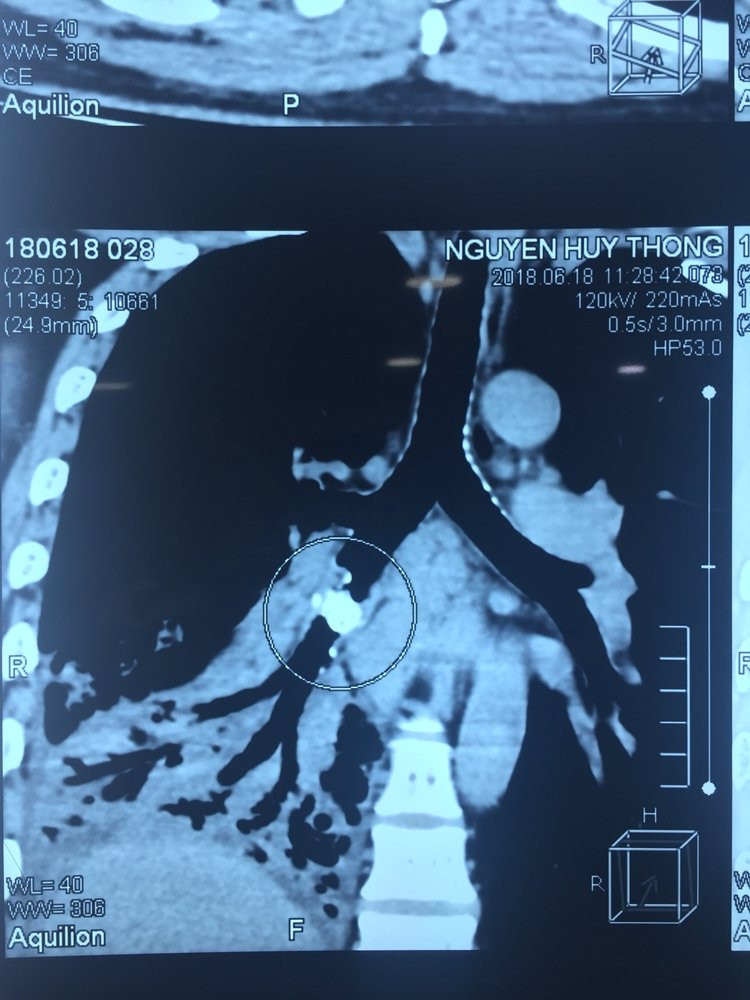

Trước đó, anh N.H.T (41 tuổi) vào BV cấp cứu trong tình trạng ho khạc đờm vàng, sốt cao liên tục trong vòng 3 ngày, cơ thể mệt mỏi. Sau khi thăm khám, ekip điều trị chẩn đoán anh bị viêm phổi thùy dưới bên phải. Tiến hành chụp CT phổi, các bác sĩ phát hiện một dị vật nằm trong phế quản của thùy dưới phổi phải. Đây chính là nguyên nhân gây ra các biến chứng viêm phổi cho bệnh nhân.

Hình ảnh dị vật trước khi mổ.